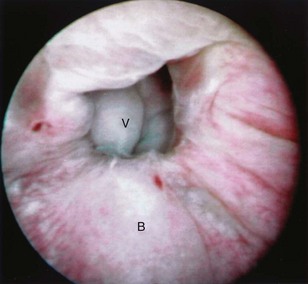

An endoscopic examination should be performed in patients with a suspicion of VVF (Fig. 77–5). Immature fistulae may appear as an area of localized bullous edema without distinct ostia. Mature fistulae may have smooth margins with variably sized ostia. In some cases, multiple pits and cavities along an area of the traumatized posterior bladder wall, in the setting of a small VVF, may make it difficult to identify the exact fistula tract. In these cases, a guidewire or ureteral catheter may be placed through the working channel of the cystoscope and into the fistula tract (Fig. 77–6). Visualization of the wire in the vagina confirms the exact location of the VVF on both the bladder and genital sides. Cystourethroscopy can confirm the presence of the fistula, but also may assess the size of the tract, the presence of collateral fistulae, and the location of the ureteral orifices in relation to the fistula. Small fistulae, usually less than 3 to 4 mm in diameter may be amenable to simple fulguration, which can be performed at the time of cystoscopy (see later discussion) (Stovsky et al, 1994). Importantly, in the setting of a prior history of pelvic malignancy, a biopsy of the fistula is often done to evaluate for the possibility of a recurrent malignancy. Fistulae located near or at the ureteral orifice may require ureteral reimplantation at the time of VVF repair. This type of requirement would usually mitigate against a completely transvaginal attempt at repair.

Figure 77–5 Endoscopic view of vesicovaginal fistula (VVF). This is the same patient as in Figure 77–4. The fistula is now seen from the bladder side. This VVF is large enough to see directly into the vagina (V) through the bladder (B).